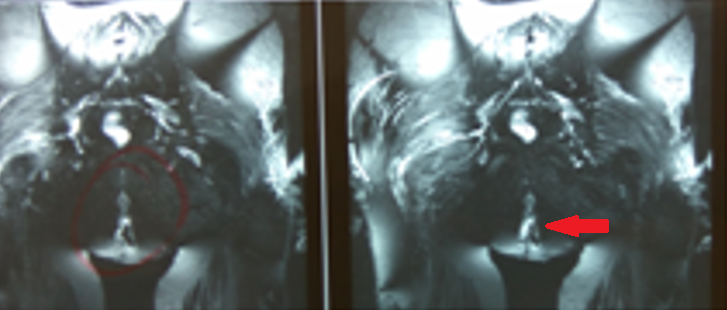

MRI περινέου. Κόκκινο βέλος — Παραορθικό συρίγγιο (Ευγενική παραχώρηση Dr. V. Penopoulos)